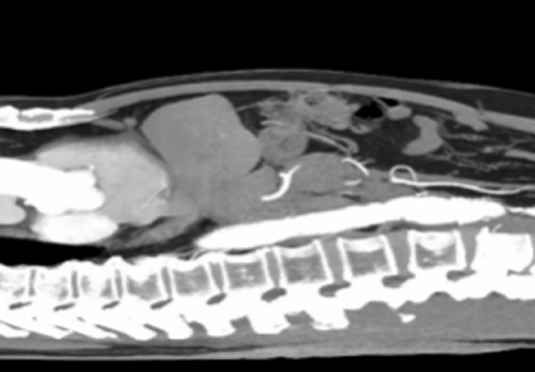

血管重生:激起四周構造中的血管成長,進程被稱為血管重生或腫瘤血管化;血管不法則散布,缺少一般布局和功效,致血液供給缺乏和缺氧環境。

構造粉碎和浸潤:侵襲和粉碎一般構造,穿過一般構造的樊籬,入侵到其余構造和器官中,構成遠處的轉移,顯現出惡性腫瘤細胞的分散才能。